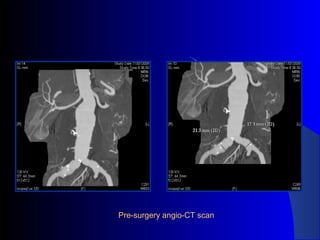

The document discusses the clinical application of the Endurant stent graft system in treating aorto-bisiliac aneurysms, detailing procedures performed on two male patients aged 72 and 73. Each patient had a history of dyslipidemia and carotid atherosclerosis, with procedures involving the bilateral bell bottom technique and the use of coils and fibrin glue. It includes pre-surgery imaging, intrasurgery angiography, and follow-up control scans to monitor outcomes.